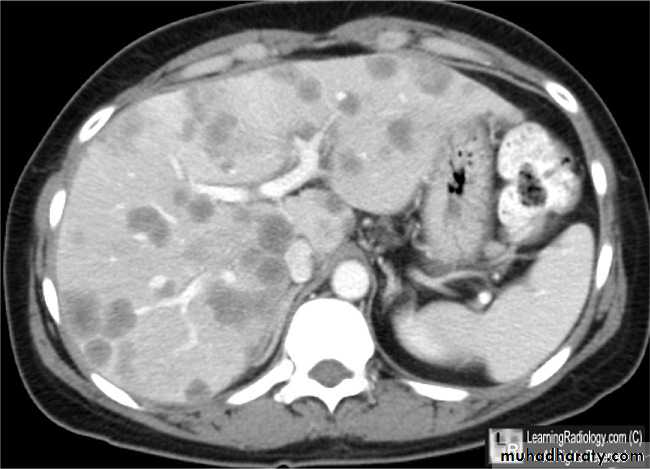

Metastases, notably from carcinoma of stomach, colon, pancreas, lung and breast are much more common than primary tumors.Metastases are often multiple, situated peripherally and of variable size.

At CT, metastases are seen as rounded areas, usually lower in density than normal liver parenchyma with intense enhancement seen after IV contrast.